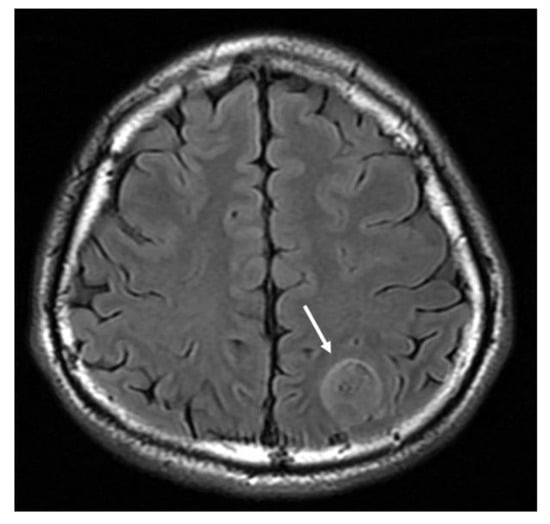

Figure 2.

MRI T2-weighted fluid attenuation inversion recovery (FLAIR) axial image demonstrates a hyperintense mass lesion (arrow).